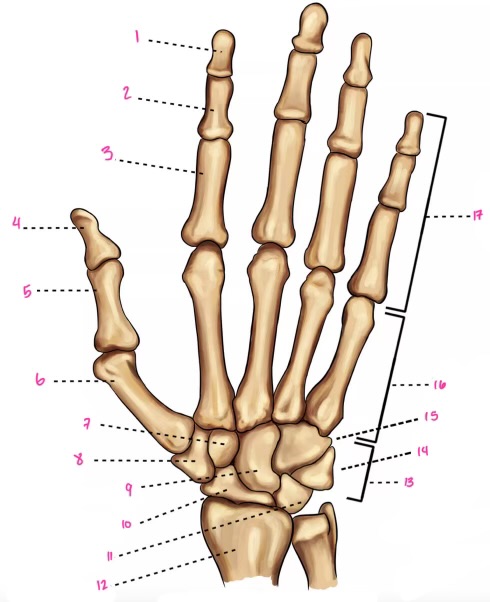

1

1

2

2

3

3

4

9

5

10

6

11

7

14

8

15

9

16

10

17

11

18

1

13

2

14

3

15

4

16

5

17

6

18

7

19

8

20

9

7

22

8

23

9

24

10

25

11

26

13

27

14

28

15

29

16

30

17